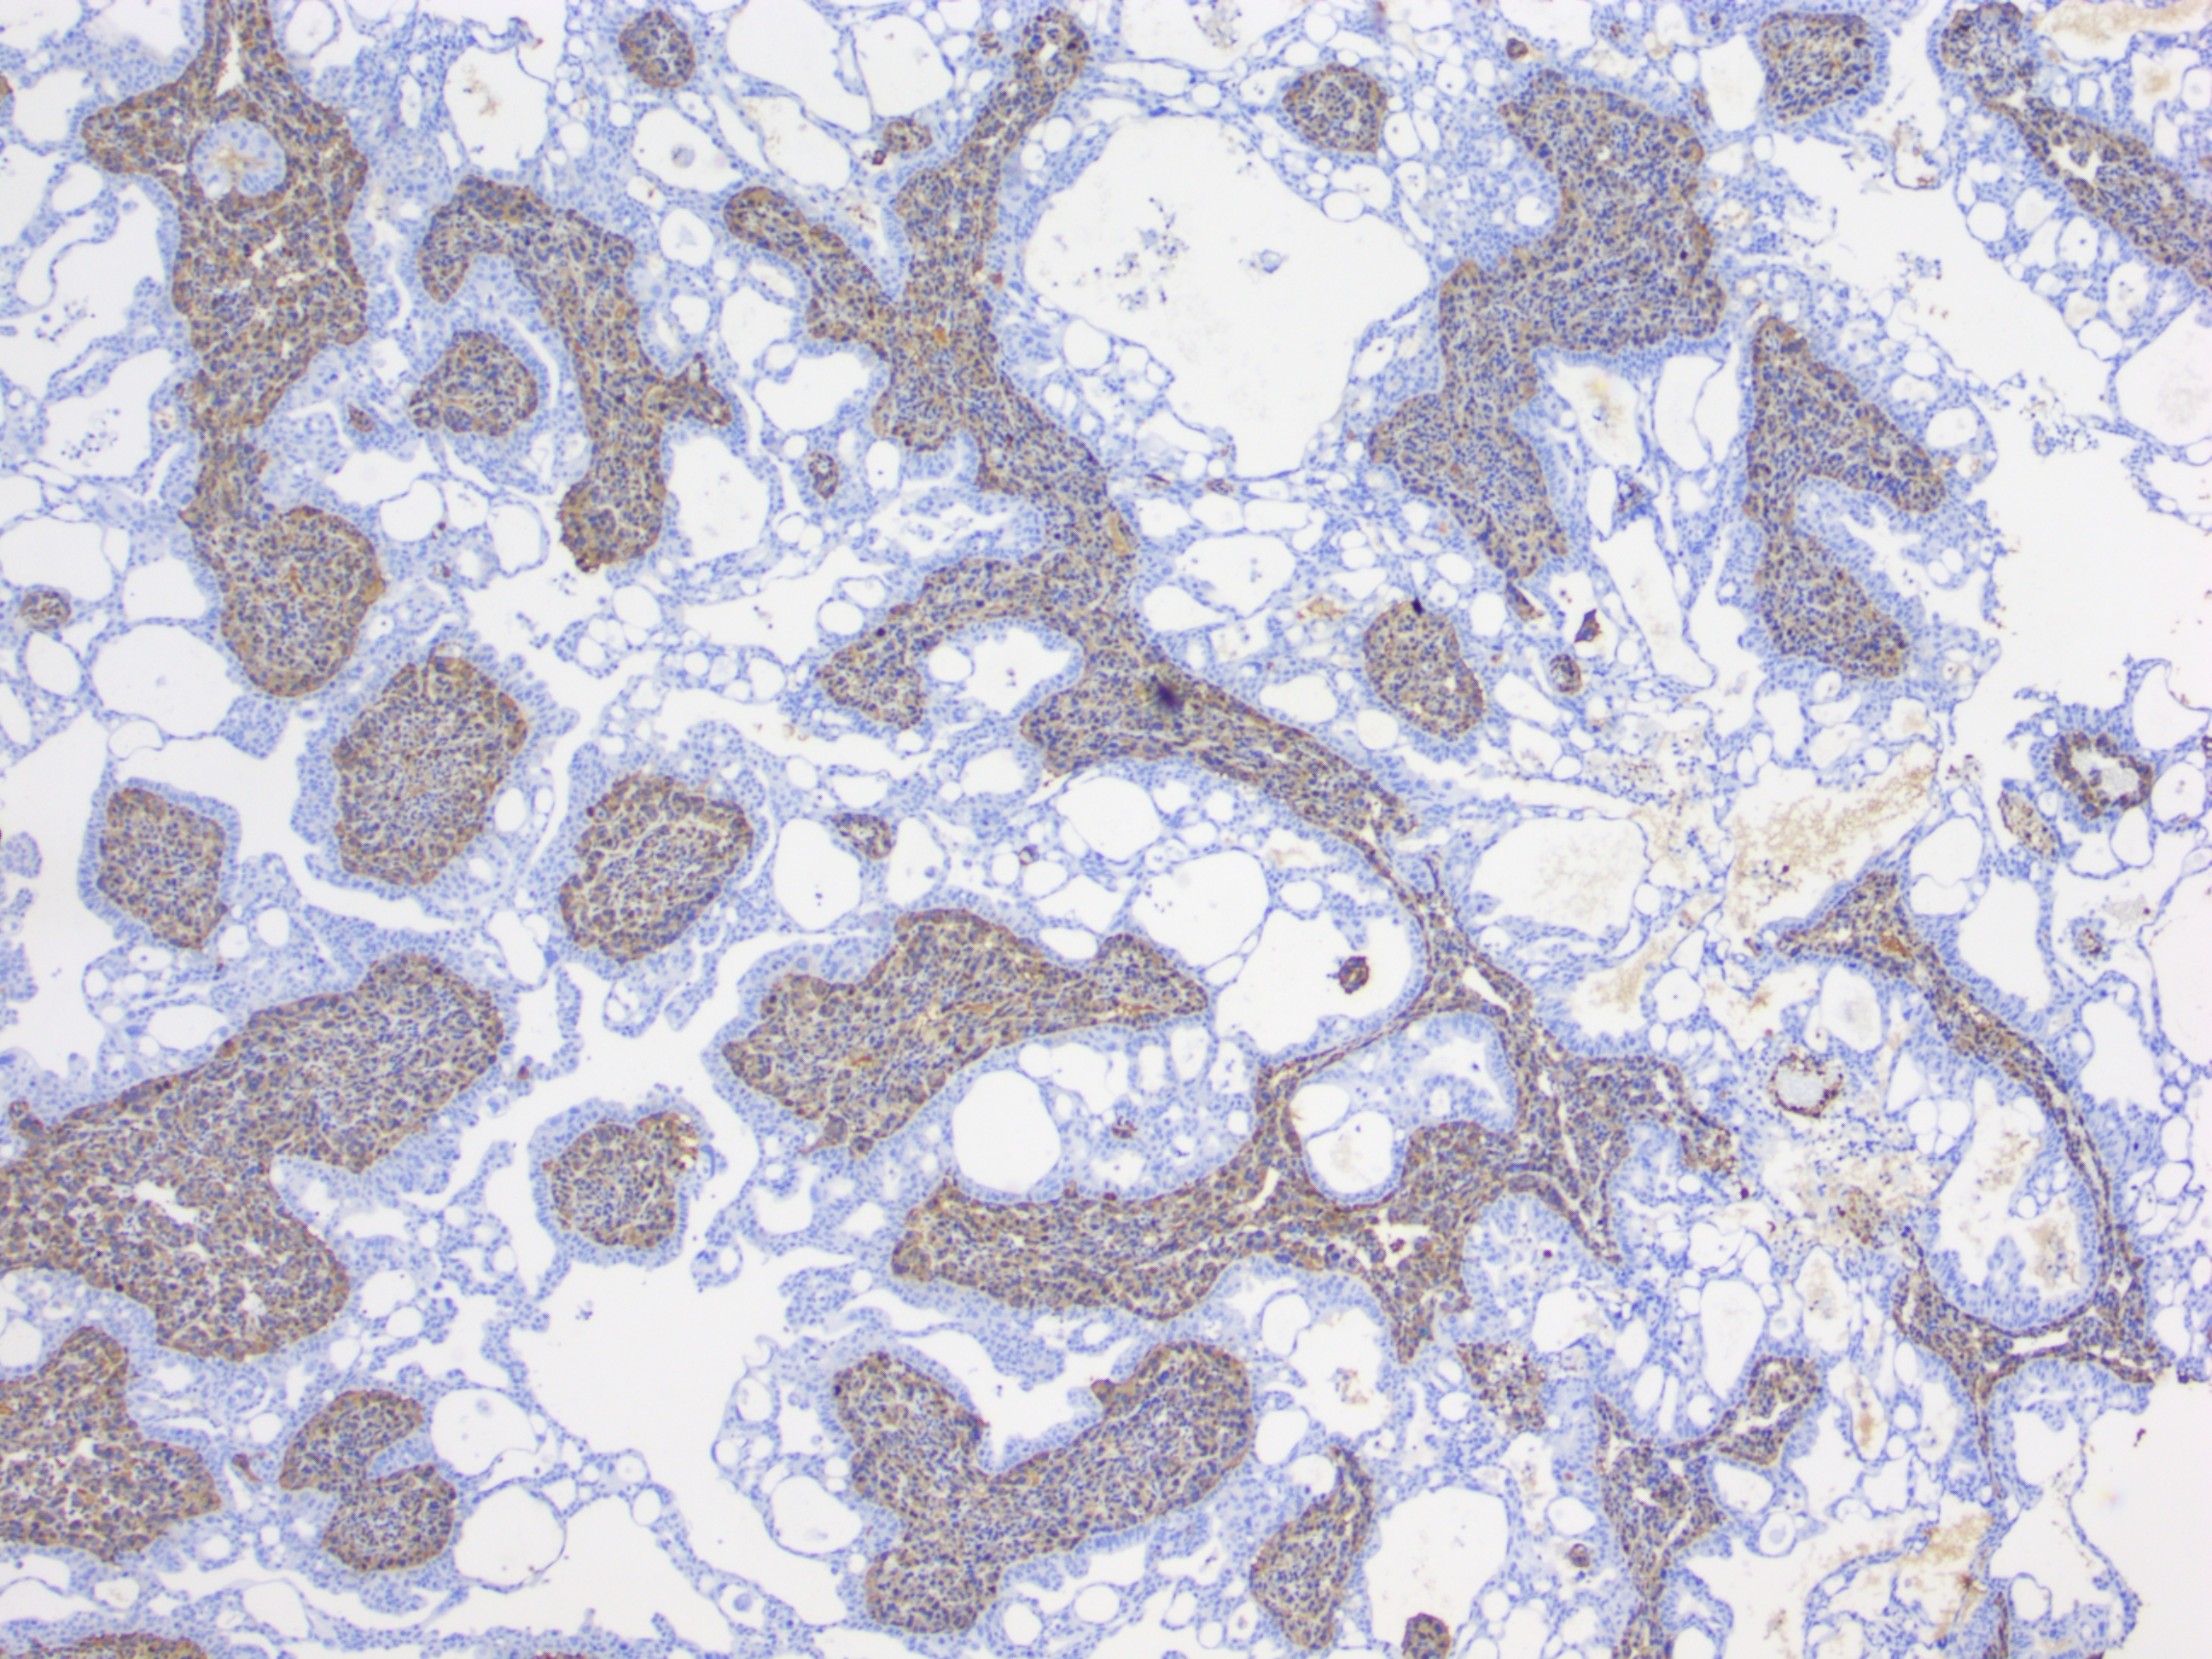

免疫组化单标染色示例

免疫组织化学